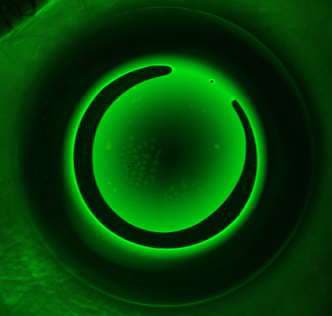

Incomplete Reverse Curve Ring

Incomplete reverse curve rings form when a lens fails to align to the peripheral cornea in one meridian. This results in an uneven ring of mid-peripheral steepening, preventing the central fluid pressure from achieving the desired corneal compression. On topography, incomplete reverse curve rings will present as an uneven “bull’s-eye” ring. The reverse curve may be incomplete in only one quadrant (Figure 2) or across an entire meridian (Figure 3).

Such topography patterns can commonly occur without issue and may not require any lens modifications. If the patient’s vision is significantly reduced, consider adjusting the peripheral toricity of the ortho-k design to resolve this issue.